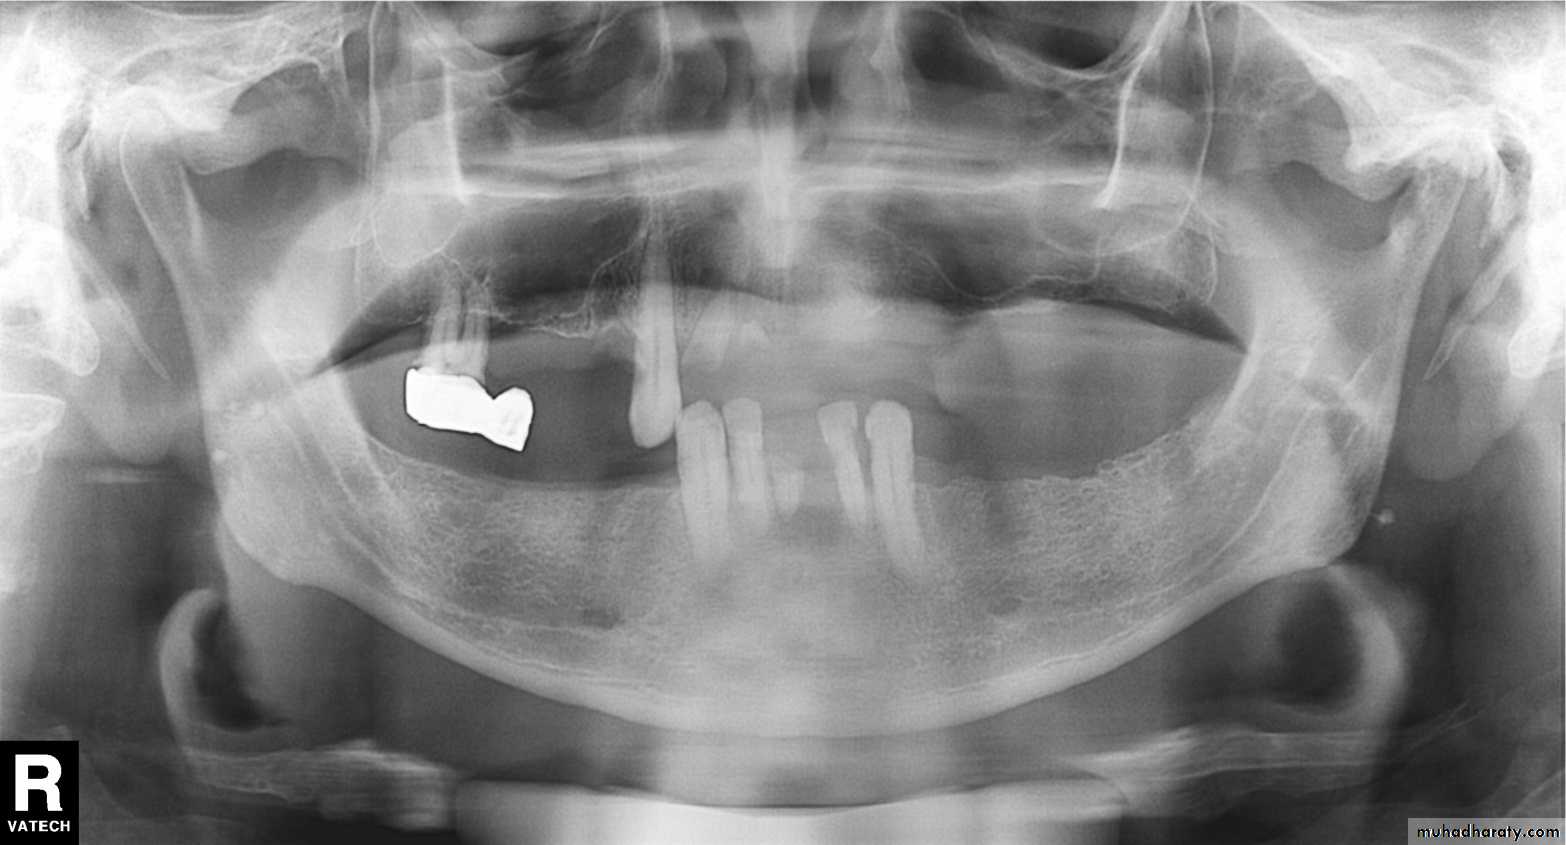

1, Mandibular condyle. 2, Articular eminence. 3, Coronoid process of mandible superimposed on zygomatic arch. 4, Posterior wall of maxillary sinus. 5, Posterior wall of zygomatic process of maxilla. 6, Hard palate. 7, Nasal septum. 8, Tip of nose. 9, Dorsum of tongue. 10, Hyoid superimposed over inferior border of mandible. 11, Inferior border of maxillary sinus. 12, Image of cervical spine. 13, Medial border of maxillary sinus. 14, Infraorbital canal. 15, Infraorbital rim. 16, Pterygomaxillary fissure. 17, Anterior border of the pterygoid plates. 18, Lateral pterygoid plate superimposed over soft palate and coronoid process of mandible. 19, Ear lobe. 20, Inferior border of mandibular canal. 21, Mental foramen. 22, Posterior wall of nasopharynx. 23, Inferior border of mandible superimposed from opposite side. 24, Soft palate over mandibular foramen of mandible.